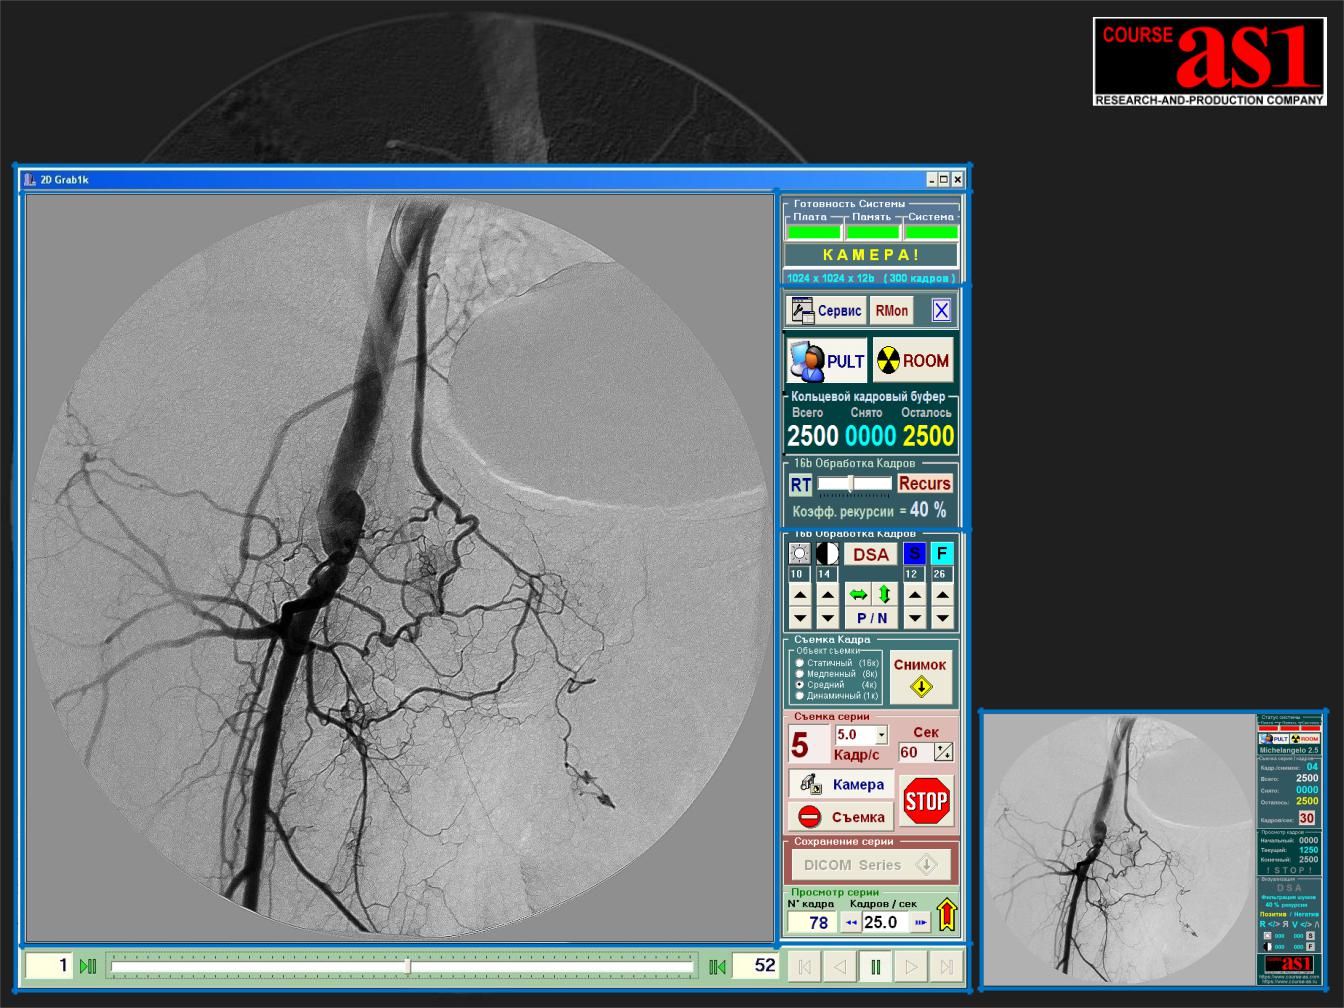

“КУРС-АС1” разработало и поставляет X-Ray Систему |

“Michelangelo” для Потоковой 2D Обработки и Визуализации |

кадров в Реальном Времени ( 1k*1k*12b при 30 кадрах/сек. ) |

Обработка и Визуализа- |

ция реального времени: |

- Первичных кадров, |

- Зонная Обработка, |

- Real Time DSA |

- Мульти-кадровая |

Слева X-Ray Система |

Реального Времени |

“AS_RTDR-1M30” |

( внизу - DSA обработка |

в формате QuickTime) |